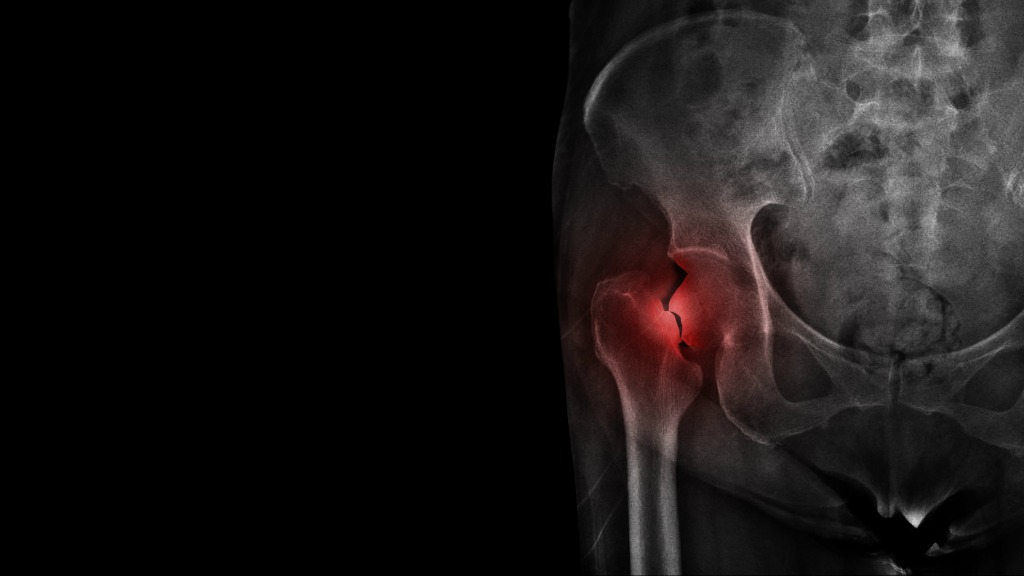

骨粗しょう症とは、骨密度が低下することで骨が脆くなり、

骨折しやすくなってしまう病気のこと。

酷いときはくしゃみや少し手をついたなどの軽い衝撃で骨折してしまうことも

あります。

さらに、2015年の研究ではCBDが骨折の治療にも役立つ可能性があることを

発見しました。

実験では、大腿骨が骨折したラットにCBDのみ、もしくはCBDと同じく

「カンナビノイド」のひとつであるTHC(テトラヒドロカンナビノール)のいずれかを投与し、その影響を観察しました。

結果、THCでは大きな効果が得られませんでしたが、CBDのみで治療した

ラットの治癒が早く、さらに同じ部位で骨折する可能性も低くなったことが

報告されました。